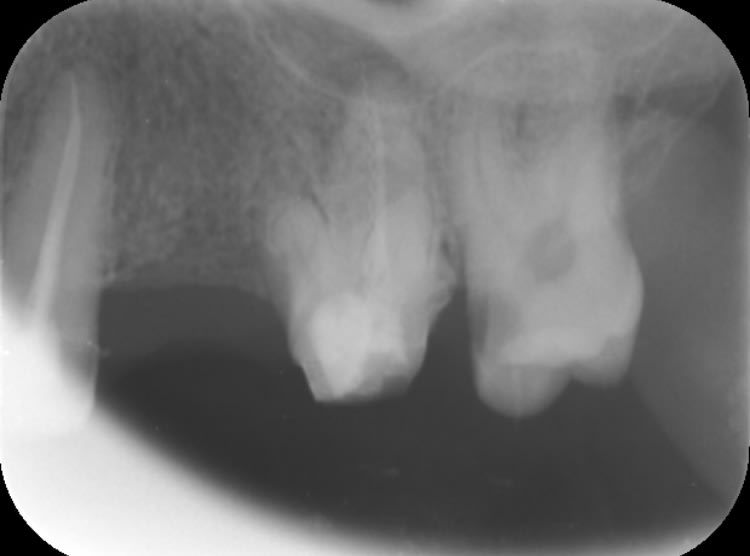

Il est où lachmar ? Cas qui a été traité par une roumaine. Il y avait un bridge que j’ai démonté avec une merde sous chaque dent.

J’ai essayé de conserver et retraiter 11 et 21 , j’attends que ça cicatrise. À la mandibule c’est pareil y a 4 dents manquantes. Plan de traitement 1 implant par dent manquante. Et chaque dents en bouche à retraiter.

La question est la suivante : est ce que je tente la conservation de la 6 avec le lentulo cassé ou je ne me casse pas le tronc et j’extrais ? As tu réussi à conserver des dents avec un lentulo cassé au delà de l’apex ?

Enlaye va rappliquer avec son extraction implantation immédiate :) , je ne peux pas le faire car le patient a déjà eu suffisamment de merdes en bouche. Faudrait pas rajouter une boulette de plus au tableau.

Photo bridge démonté

11 21 avant traitement

11 21 juste après retraitement

Radio de la 6 avec le lentulo

> Photo bridge démonté

> 11 21 avant traitement

> 11 21 juste après retraitement

> Radio de la 6 avec le lentulo

cher junior

ce cas aurait pu être traité par n'importe quel dentiste malhonnete

pour le lentulo chirurgie apicale et obturation retrograde